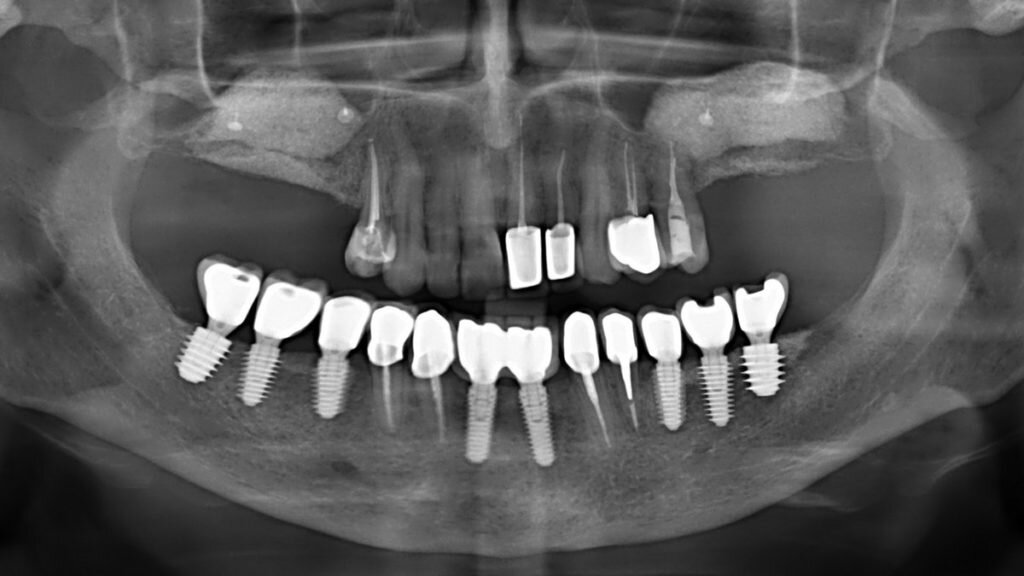

Когда по каким-то причинам человек теряет зуб, в челюсти образуется дефект, стоматолог должен решить вопрос об адекватном замещении этого дефекта. Для решения этой задачи наиболее эффективным методом является имплантация зубов.

Существует несколько методик протезирования в таких случаях, но альтернативным и более эффективным методом является имплантация зубов. При имплантации зубов соседние зубы не обтачиваются, а просто ставится имплант в место потерянного зуба и на нем делается коронка.

Вторая большая проблема, связанная с удалением зубов – это то, что потеря зубов в большей или меньшей степени сопровождается резорбцией кости. Появляется очень большая разница между уровнем кости в области потерянного зуба и в области соседних зубов. После имплантации зубов резорбции кости не наблюдается.

• Зубные импланты могут использоваться как опоры для постановления мостовидного протеза при восстановлении больших дефектов зубного ряда.

• Зубные импланты дают возможность изготовить несъемные протезы на полностью беззубой челюсти.